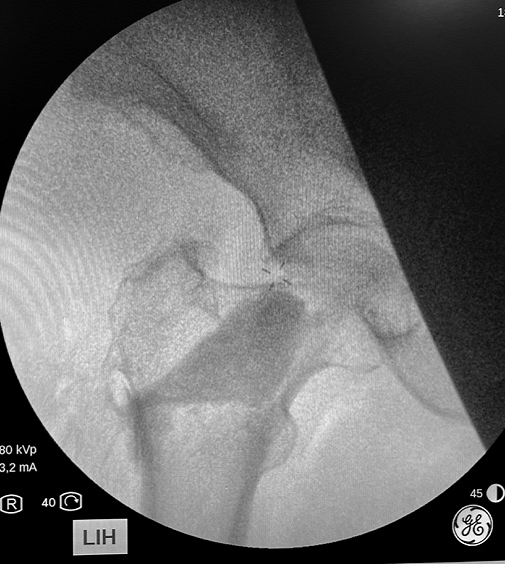

Actualmente tenemos la posibilidad de mejorar la resistencia del hueso y prevenir las fracturas de las personas mayores. Lo hacemos con una simple inyección dentro del hueso de una sustancia cálcica especial (OSSURE LOEP) que le fortalece y estimula la regeneración del hueso propio. Este efecto es inmediato, a diferencia de la medicación, que tarda meses o años en conseguirlo.

El producto OSSURETM LOEP se INYECTA EN EL HUESO para RELLENAR Y formar hueso nuevo en áreas del esqueleto OSTEOPOROTICO QUE PRESENTA MULTIPLES PEQUEÑAS CAVIDADES VACIAS. ESTE material biorreabsorbible, Y osteoconductor ESTÁ HECHO A BASE DE CALCIO. El procedimiento de mejora ósea local es un procedimiento mínimamente invasivo. Se inyecta en sitios preparados quirúrgicamente OSSURE donde se endurece, se reabsorbe y se reemplaza con hueso nuevo.

Ejemplos de algunos casos ya operados